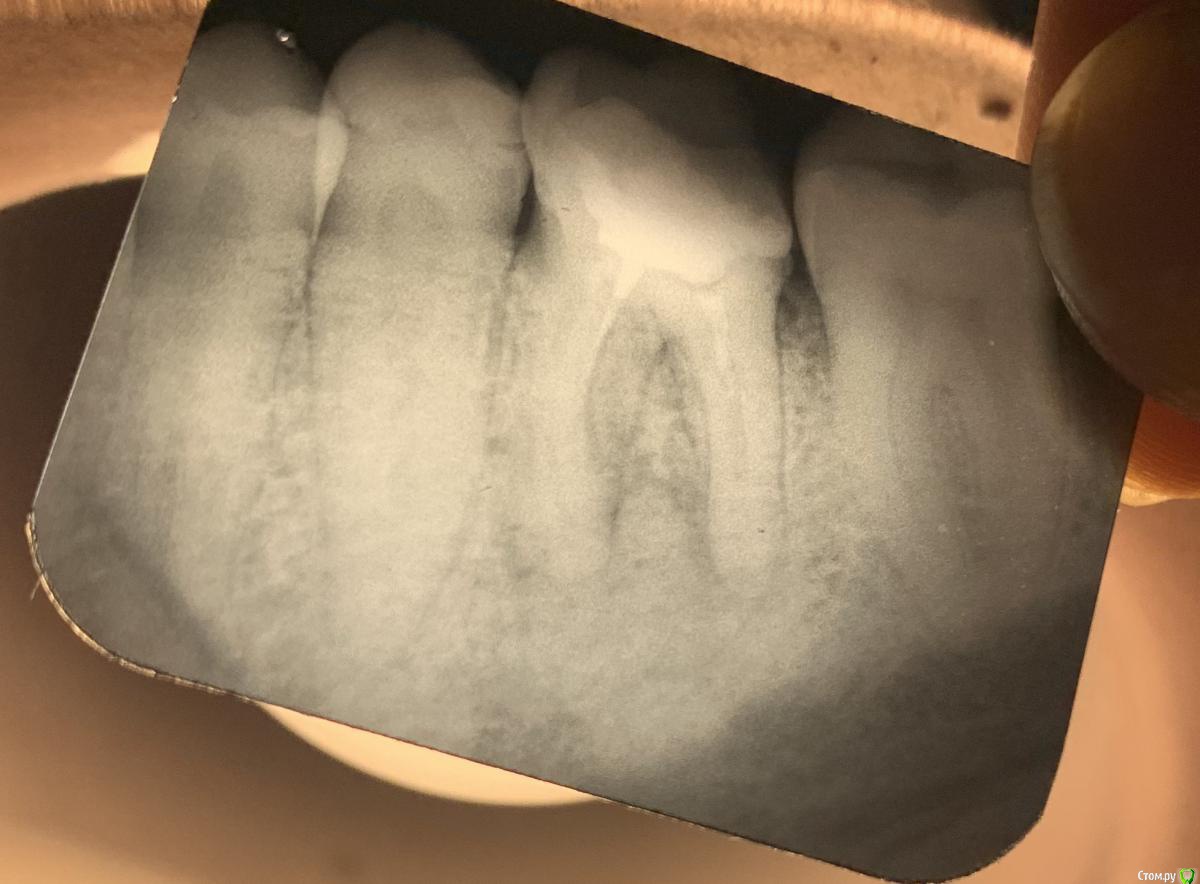

lodo4nik Опубликовано 7 июля, 2020 Поделиться Опубликовано 7 июля, 2020 Добрый день! Прошу помочь с решением судьбы зуба.На панорамном снимке мой стоматолог обнаружил новообразование в районе 36 зуба. Говорит причина в плохо залеченном канале-не вычистили все до конца при лечении.Этот зуб лечил около 10-15 лет назад (сейчас мне 35) в городской гос. поликлинике. Жалоб на него никаких нет и не было-не болит, не реагирует на холодное/горячее, выделений в районе зуба нет.Для уточнения сделали точечный рентген.Мой стоматолог советует зуб удалять и через пол года ставить имплант-т.к. будем сохранять зуб-сохраним новообразование. Сейчас это доброкачественное образование, которое со временем может перерасти в злокачественное. Во втором медцентре-хирург однозначно сказал удалять.В третьем медцентре сказали, что зуб можно спасти, но для уточнения отправили на КЛКТ. Посмотрели и сказали, что это киста и она уже очень разрослась-зуб под удаление, не спасти.Отправил снимки в четвертый медцентр, в столице (сам я живу в областном центре), знакомый посоветовал их-сказал что сохранили зуб, когда все остальные врачи настаивали на удалении. Оттуда пришел ответ-приезжайте, перепломбируем каналы, сохраним зуб. Но они КЛКТ не смотрели.Я в растеряности-что делать. Помогите окончательно определиться.И еще дополнительный вопрос. У меня повышен С реактивный белок высокочувствительный последние лет 8, не значительно, но постоянно 1.5-2.5 (референс <1) . Причина может быть в этом зубе?Ссылка на КЛКТ:https://yadi.sk/d/bVoEJ3dM53D3CAАрхив с КЛКТ:https://yadi.sk/d/YkVkCMyxDQsXQAФото без сжатия:https://yadi.sk/d/_LrW1Gt7YADgFQЗаранее спасибо! Ссылка на комментарий

red_butler Опубликовано 9 июля, 2020 Поделиться Опубликовано 9 июля, 2020 Я в растеряности-что делать. Помогите окончательно определиться. Здравствуйте, новообразования нет, это банальный периодонтит, для принятия решения нужно очно или по фотографии оценить оставшийся объем твердых тканей, если зуб возможно восстановить, то повторное лечение корневых каналов, если нет, то удаление 2 Ссылка на комментарий